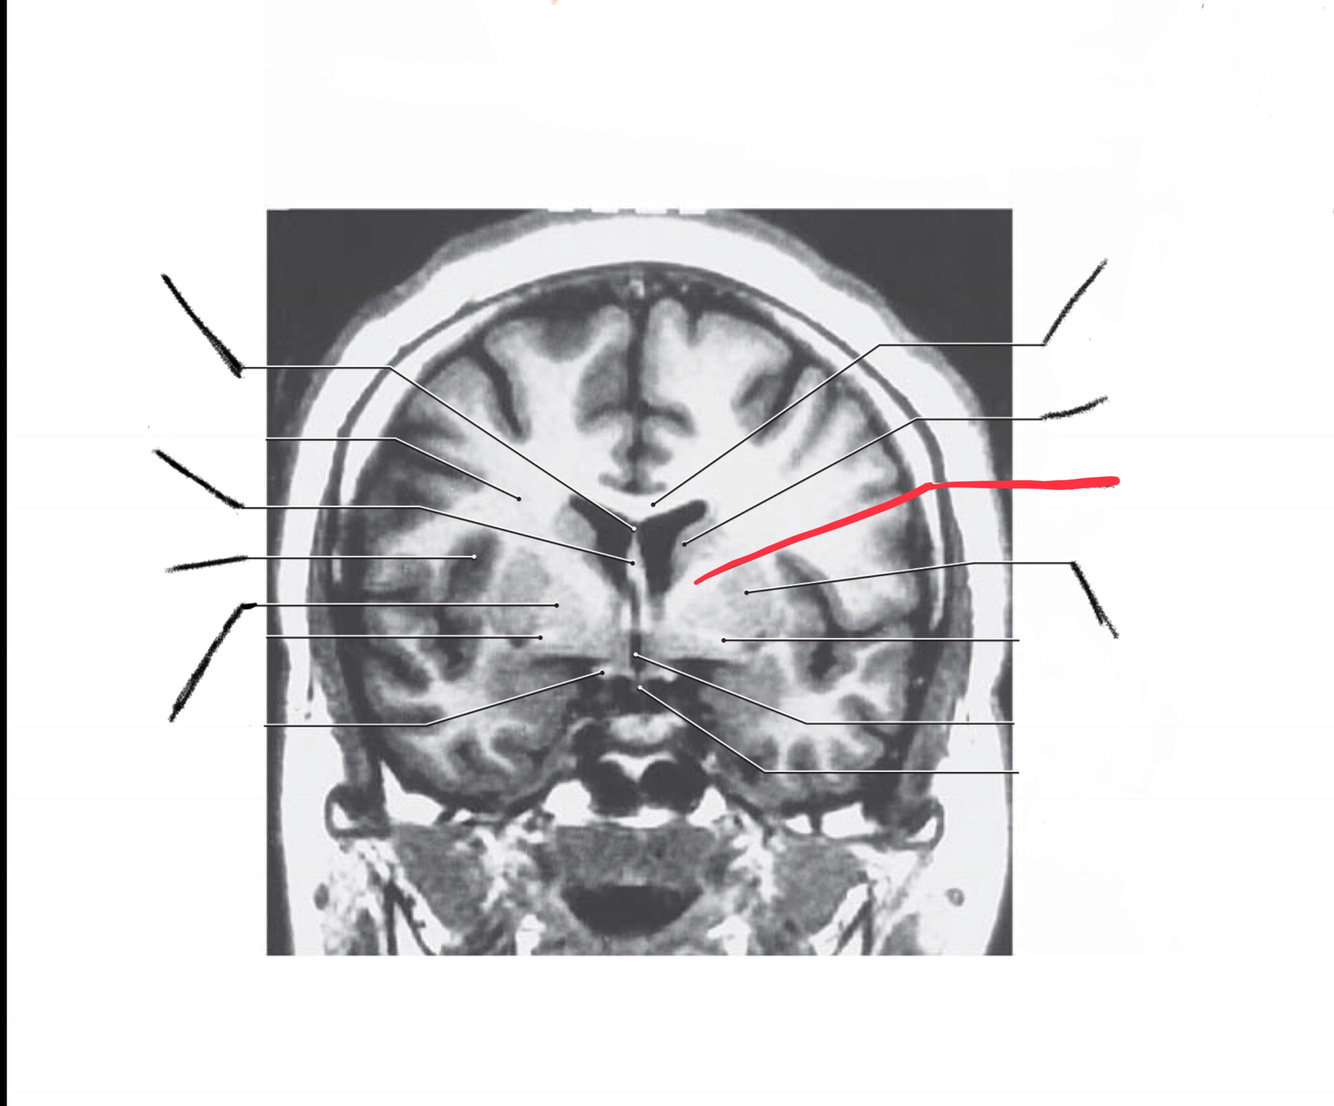

The structure indicated by the red line is?